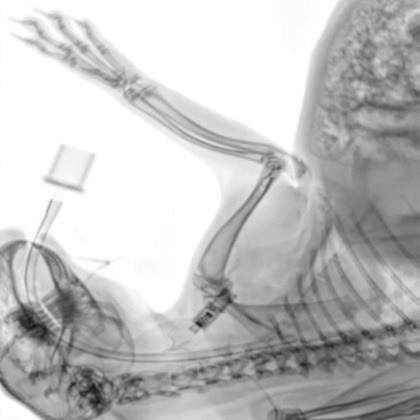

Intraoperative control image of a rabbit. The position of the intubation can be determined with great precision. Image Credit: Scintica Instrumentation Inc